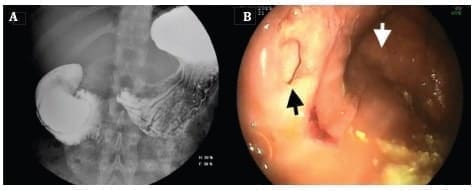

Se realizó un nuevo tránsito gastrointestinal y EVDA (Figura 1), donde se observa un divertículo duodenal intraluminal gigante a nivel de la segunda porción, que condiciona una oclusión duodenal con dilatación del duodeno proximal. Ante los hallazgos, se decide nuevamente tratamiento quirúrgico programado.

Figura 1. A) Segundo estudio de tránsito gastrointestinal con bario, donde se observa un divertículo duodenal intraluminal gigante, que condiciona oclusión duodenal con dilatación del duodeno proximal. B) En la endoscopia, la flecha blanca marca el saco del divertículo y la flecha negra, la verdadera luz duodenal.